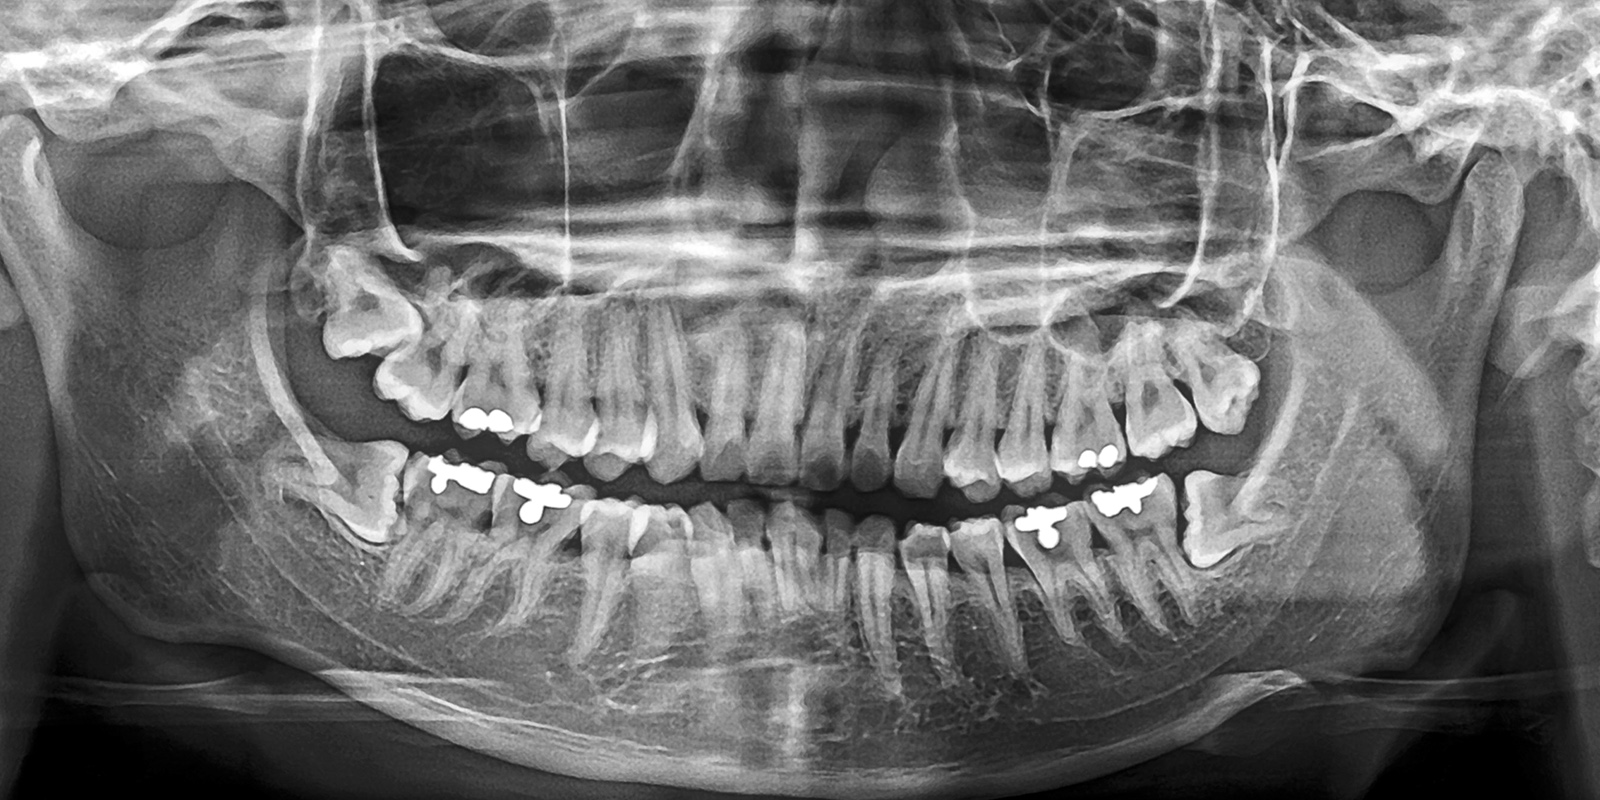

「パノラマレントゲン」でお口全体を把握

広範囲を撮影でき、お口全体を1枚で確認できる「パノラマレントゲン」により、親知らずの向きや位置、周囲の歯との関係を把握します。

特に下あごの親知らずでは、下歯槽神経との位置関係が重要となるため、神経損傷のリスク評価に欠かせない検査です。